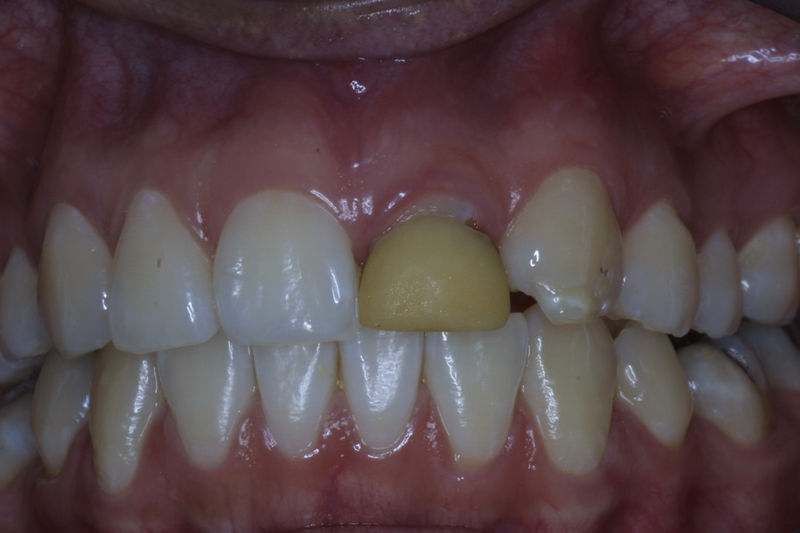

Restauraciones fabricadas en el laboratorio con materiales estéticos, los cuales cubren de manera total dientes anteriores y posteriores. Se utilizan primariamente para restaurar dientes con caries, fracturas y/o defectos amplios, así como soportes de puentes. Para poder enviar el caso al laboratorio se toman impresiones utilizando materiales de impresión o técnicas modernas digitales.

Amplia gama de tratamientos para mejorar la apariencia de la sonrisa, corrigiendo el color, la forma, el tamaño, la alineación y la posición de los dientes. Los procedimientos más comunes y solicitados incluyen el blanqueamiento dental, las carillas y coronas, así como las resinas.

La restauración de un diente tras una endodoncia, es crucial para su supervivencia a largo plazo, ya que el procedimiento puede debilitar la estructura dental. El tipo de restauración elegido depende principalmente de la cantidad de estructura dental remanente después de la endodoncia. Principalmente se usan incrustaciones, coronas y/o postes.